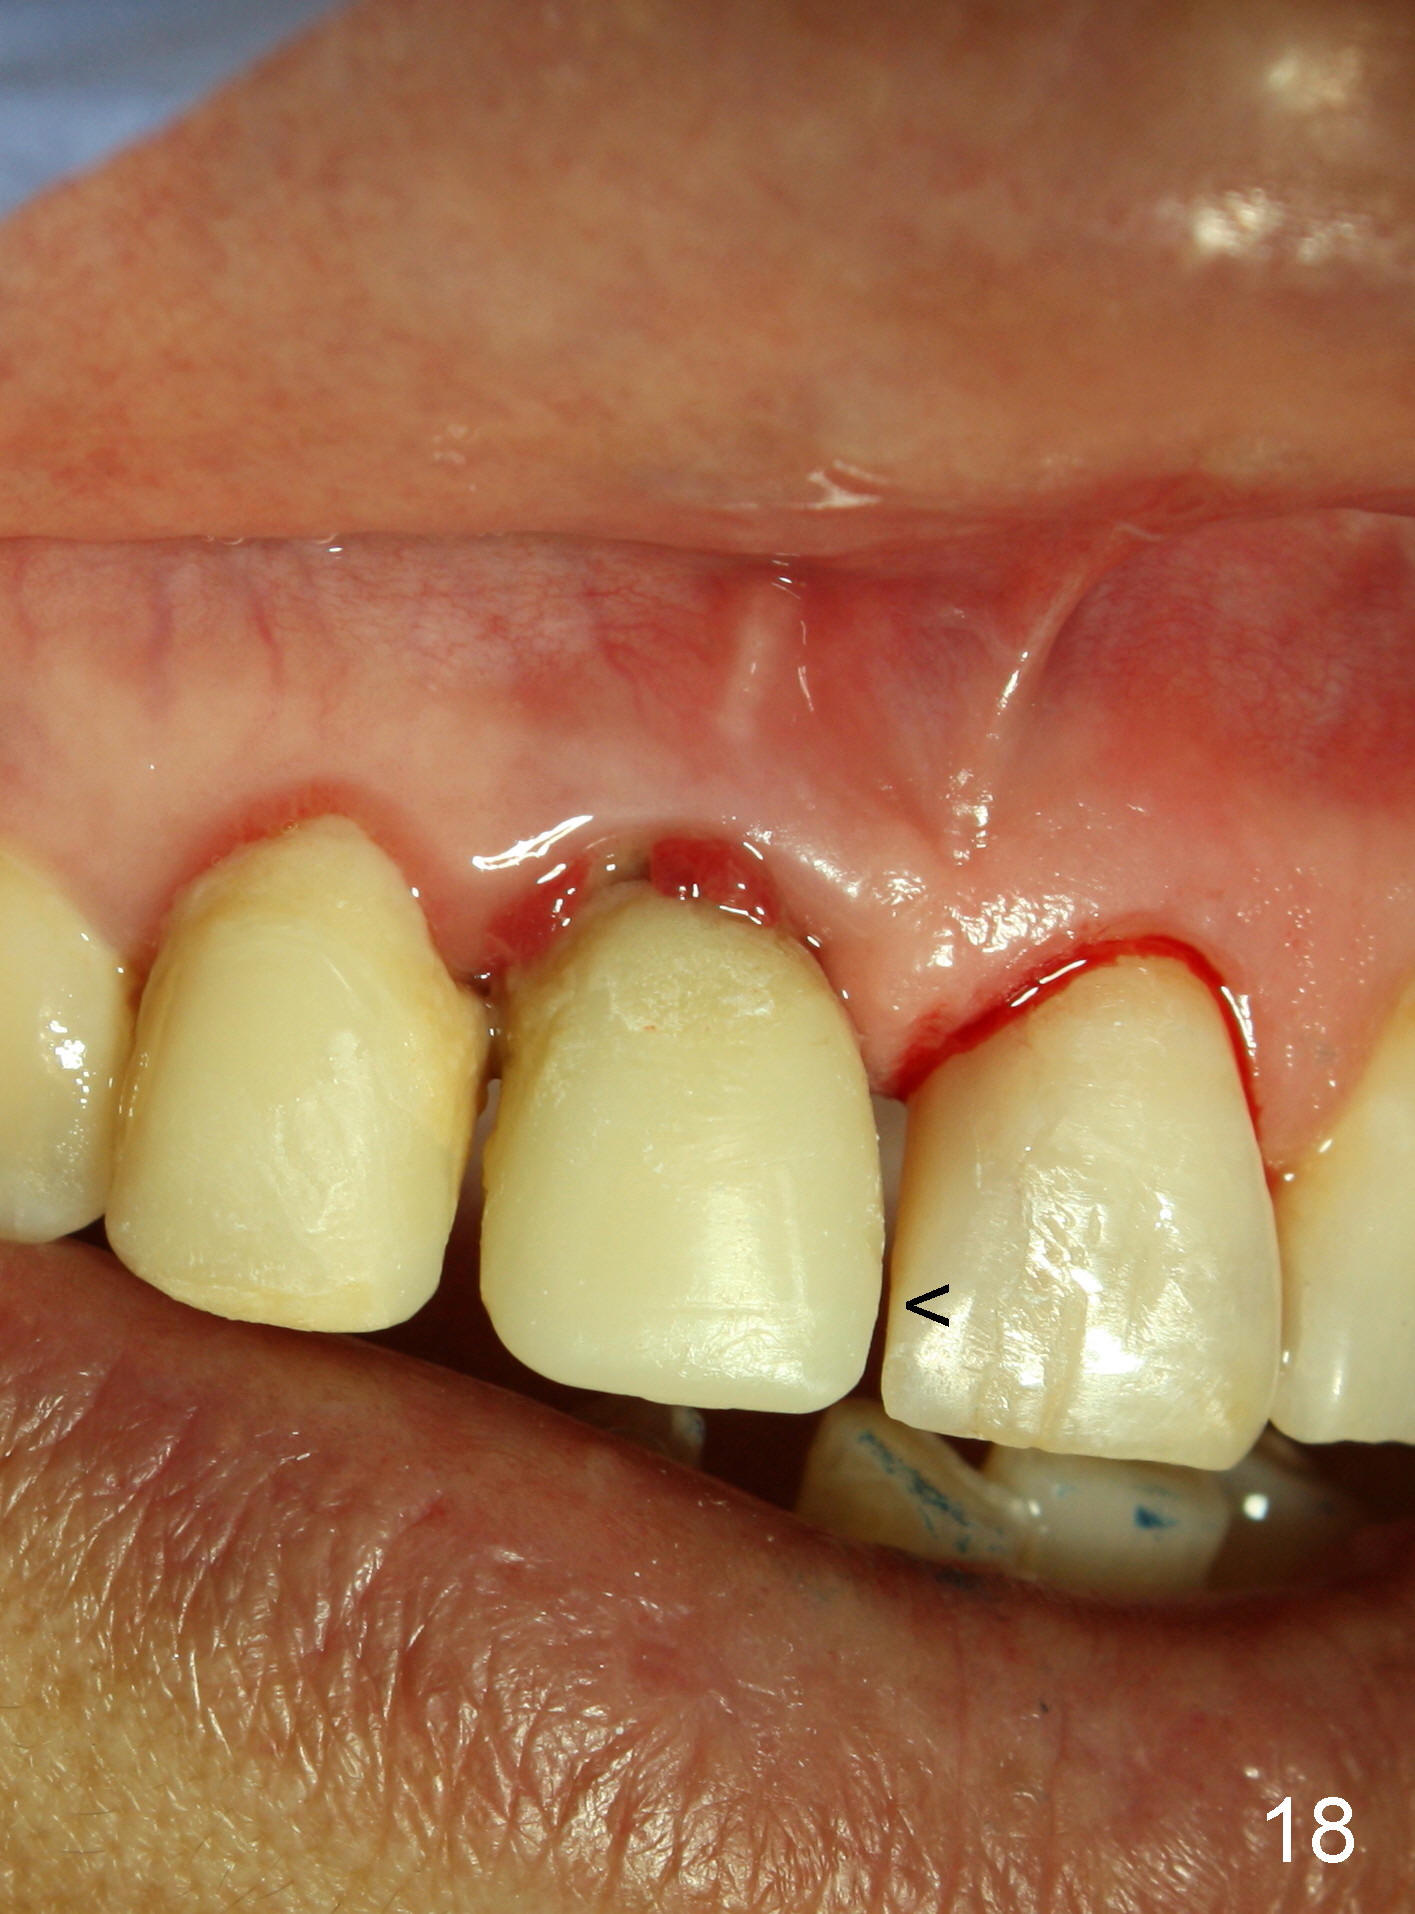

Four-month follow up shows that bone graft from the tuberosity appears to have healed with the implant microthreads (Fig.17 *); there is a diastema between #8 and 9 (arrowheads). Before removal of the provisionals of #7 and 8 for final impression, new composite is added to the mesial surface of #9 as the first step of closure of the diastema (Fig.18 <).